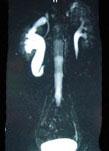

问题 男,20岁,右腰部胀痛不适,MR如图示,下列说法正确的是 ( )

选项 A、考虑为右侧腔静脉后输尿管 B、考虑为右侧输尿管自身的扭曲 C、右侧输尿管上段扩张积水 D、右侧输尿管走行异常,呈“S”形向中线移位 E、右侧肾盂积水

答案 ACDE